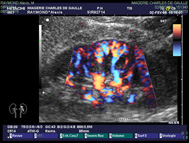

| ECHO-DOPPLER COULEUR |

| L’utilisation du flux couleur permet aussi d’analyser

la circulation sanguine. |

| Cette même sonde utilisée pour l’échographie,

permet de visualiser la paroi de l’artère avec d’éventuels dépôts, son diamètre avec un éventuel rétrécissement; |

permet de visualiser l’élasticité de la veine, avec la présence d’un éventuel thrombus (phlébite). |

| Toutes les artères et veines de l’organisme sont analysables par l’écho doppler couleur, certaines (intra-cérébrales) nécessitant des sondes spéciales. |